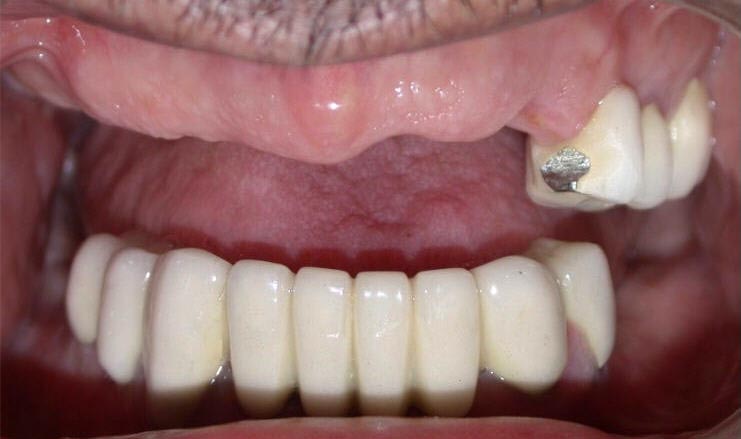

After